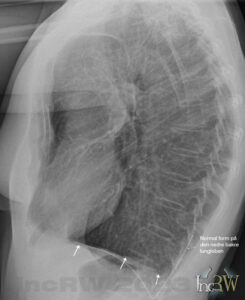

Diafragmans form kan vara olika hos olika individer utan att detta innebär att något är fel. Långa och smala personer har ofta mer utmärkande diafragmavalv med långt bakåtgående lungspetsar (lung-/pleurasinus) än hos överviktiga eller korta personer som får en mer utplanad valv/båge men som trotts detta utgörs av helt friska lungor.

Det förekommer ofta att en lungröntgen ger missvisande fynd av patologi som beror på en dålig inandning vid bildtagningen. En dåligt inandad bild kan medföra att diafragmavalven står högt och ger förtätning av lungvävnad, förstorat hjärta, mm. Vid en ny bild med optimal inandad bild, där diafragman dras ner mot buken bättre, kan röntgenbilden visa helt normala lungor.

Det finns sjukliga tillstånd som kan ge en mer avplanad diafragma eller en minskning av lungspetsen (pleurasinus) på röntgenbilden. Det kan vara vätska i lungsäcken (pleurit), pleuraadherenser1Lungsäcken nere i lungsinus kan växa ihop (pleuraadherens) efter tex. lunginflammation som då kan ses som plan diafragma på den drabbade sidan. Pleuraadherenser brukar dock ge typiska symtom i form av smärta vid andningsrörelser, långvarig hosta, viss andfåddhet, då de båda plaurabladen inte glider fritt mot varandra vid andning. Adherens i lungsinus kan även vara helt symtomfri. , vätska i buken (ascites), meteroism2Uppdriven buk som kan bero på mycket gaser i tarmarna., stor lever eller mjälte eller båda (hepatosplenomegali), fel på nervus phrenicus3Nerv som drar samman diafragmamusklerna vid inandning., lungemboli, subfreniska abscess4Varansamling i bukhålan under diafragman., stor tumör i buken, emfysem samt KOL5Kronisk obstruktiv lungsjukdom som kan innebära andningsbesvär med hosta och ökad slembildning i luftvägarna.. KOL kan även drabba icke rökande personer pga. passiv rökning, exponering av gaser/irriterande ämnen (i arbetet, etc.) och tidigare lunginflammation, mm. Vid uttalad emfysem kan man ibland även se att bröstkorgen tar en ”tunnliknande form”, som kan ses på sidobilden, med en ökad mängd luftförande vävnad bakom bröstbenet samt ofta med ett litet hjärta.